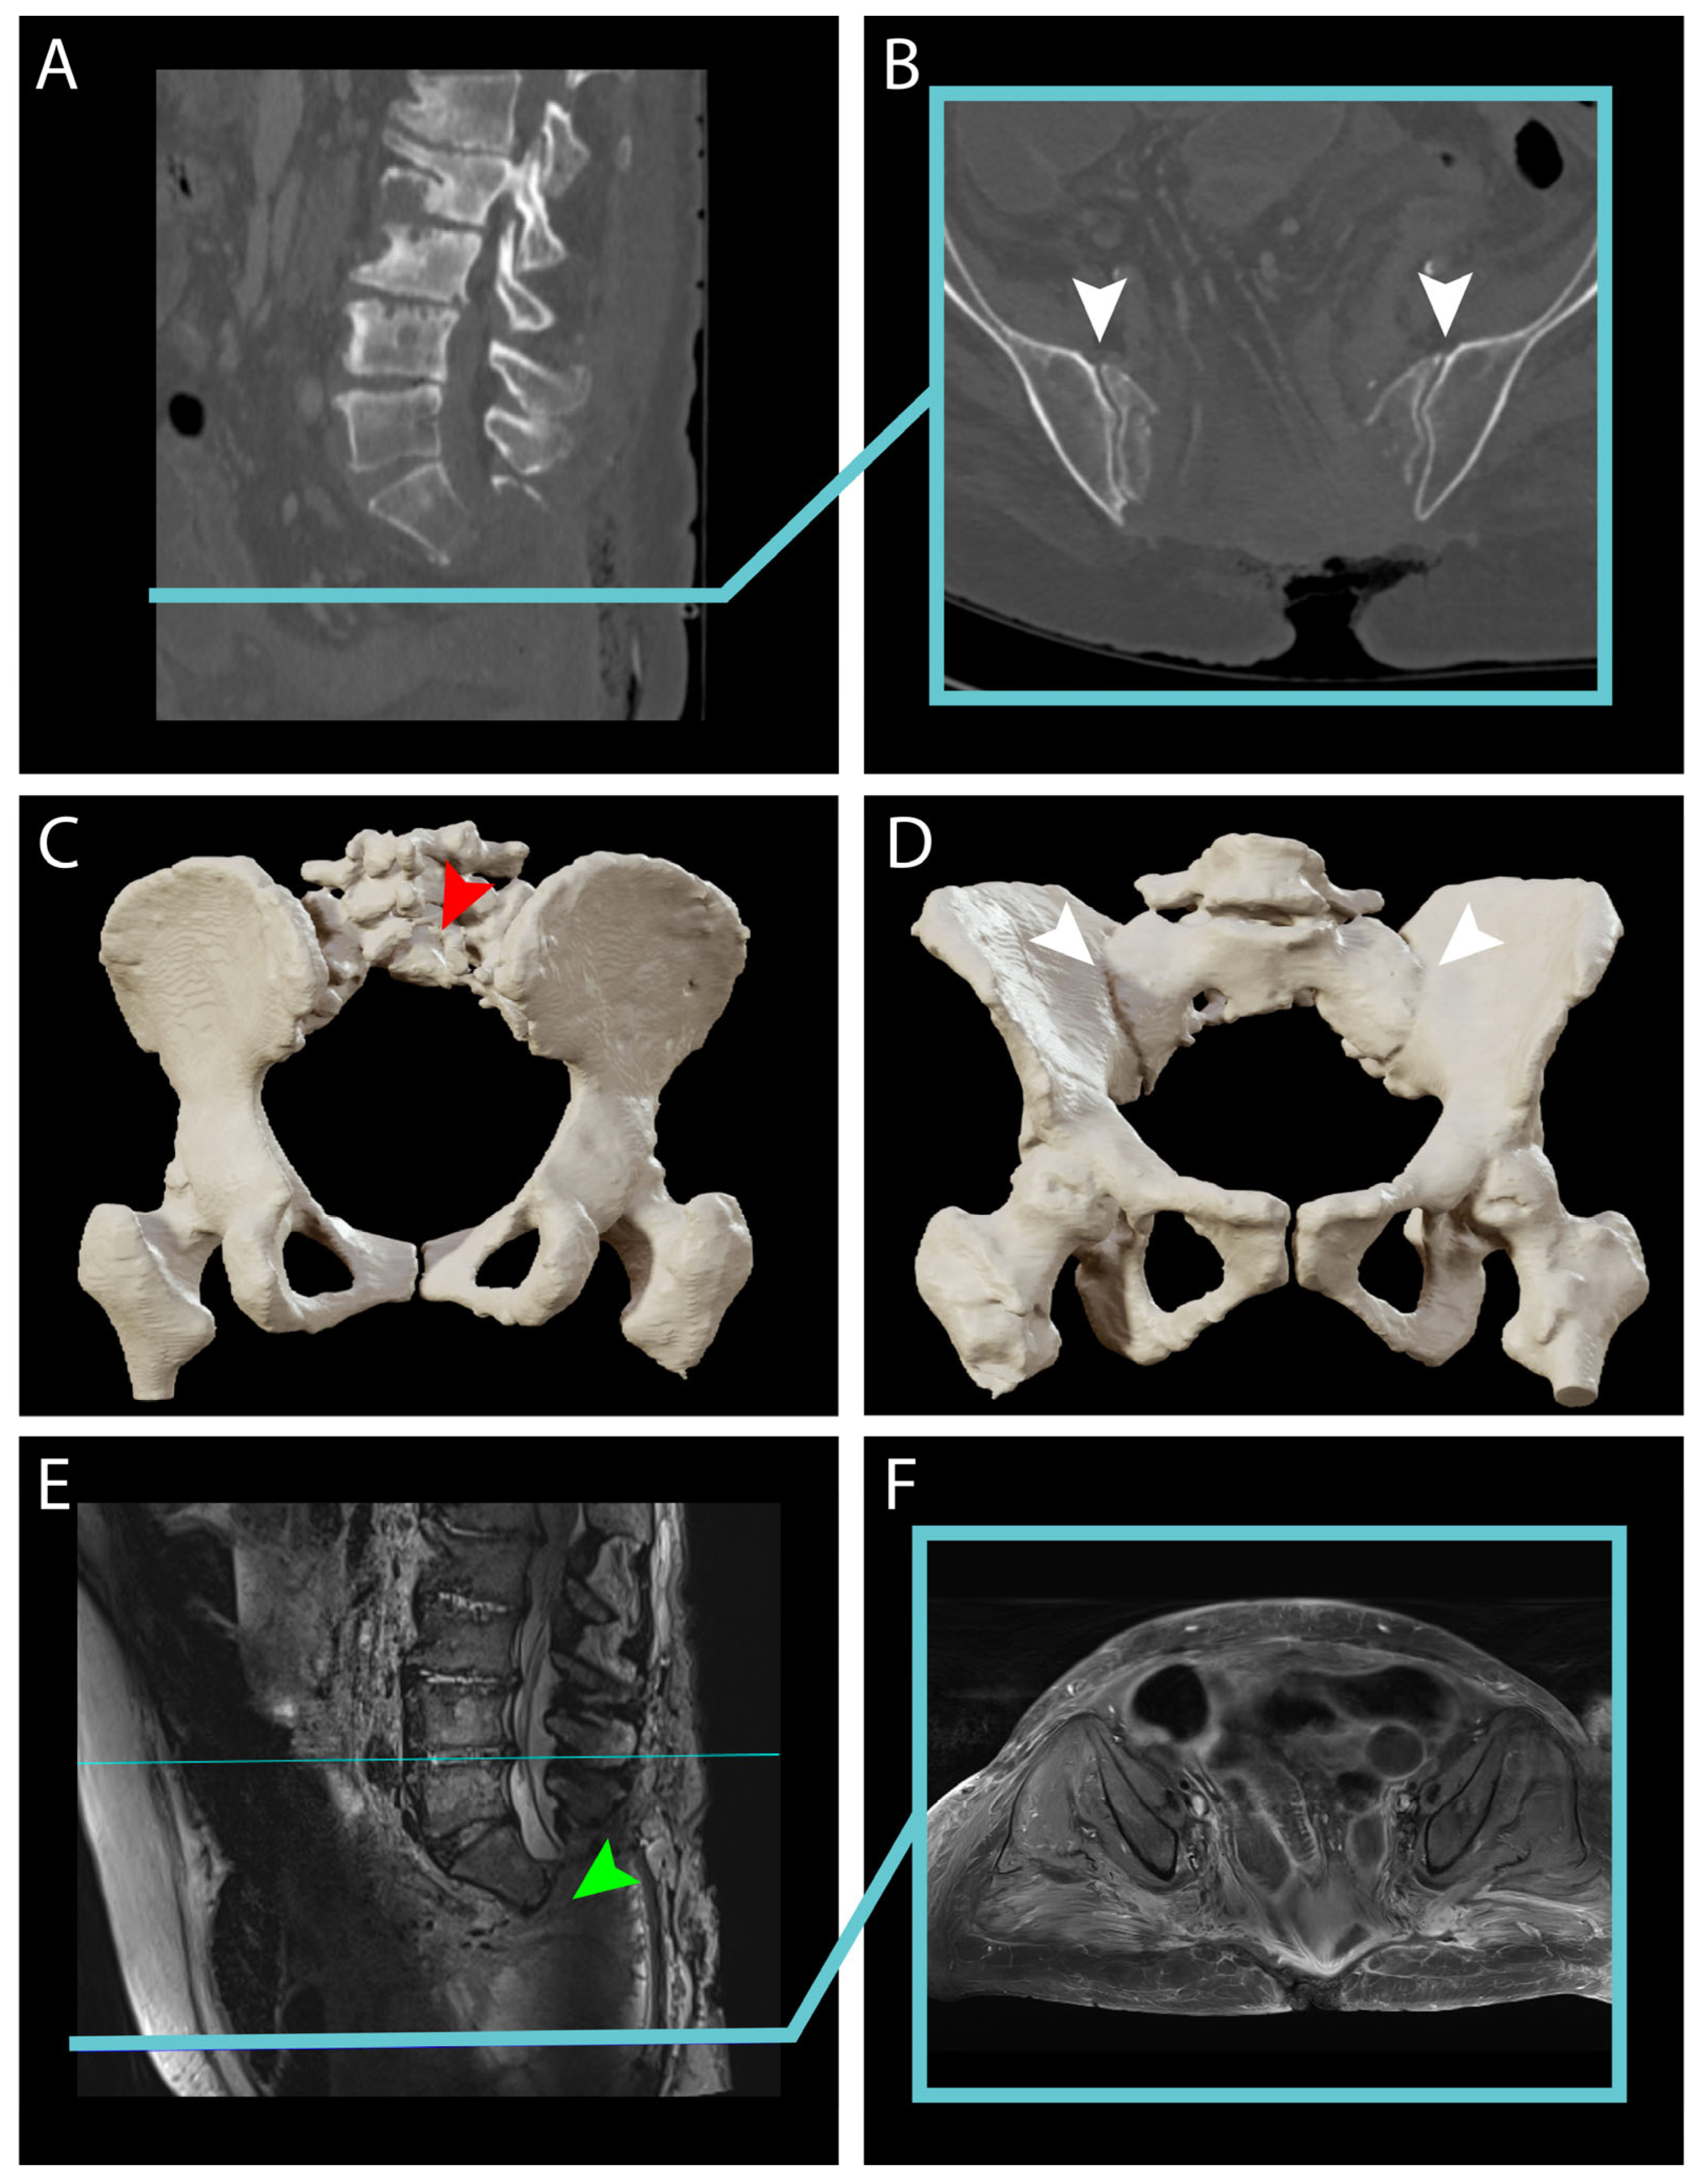

4.2. Preoperative Planning